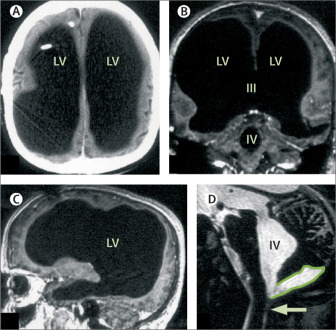

En lugar de tejido cerebral, su cráneo estaba casi completamente lleno de líquido, una condición conocida como hidrocefalia, o «agua en el cerebro». Esta condición, que ocurre cuando el líquido cefalorraquídeo se acumula y ejerce presión sobre el cerebro, había dejado al hombre con apenas un pequeño porcentaje del tejido cerebral que se esperaría en una persona normal. A pesar de esto, su vida seguía su curso, con un coeficiente intelectual de 84, ligeramente por debajo del promedio, pero no lo suficientemente bajo como para impedirle funcionar en la sociedad.